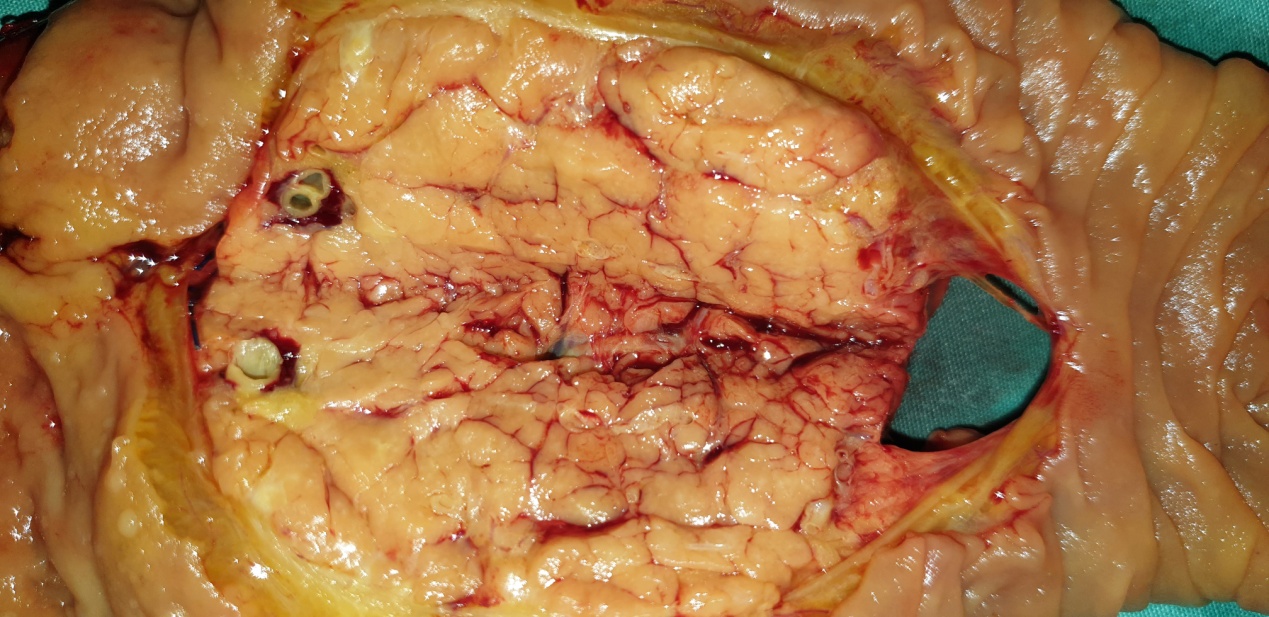

Epithelial splenic cyst. The trabeculated internal surface is visible, which may exhibit various types of epithelial lining (Courtesy Dr. V. Penopoulos)